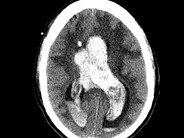

Superficial bleeding in AHA

Superficial bleeding in AHA. Superficial bleeding is common in AHA and will often resolve without hemostatic therapy. The risk of thrombotic complications associated with bypassing agents needs to be weighed against the benefit of treatment, especially in patients with additional risk factors for thrombosis. In contrast, other types of bleeds need prompt treatment.